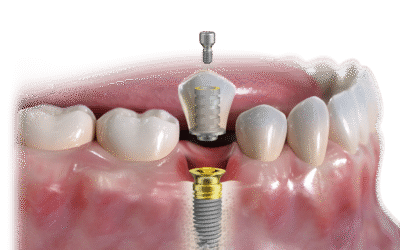

從單顆缺牙到全口重建 提供多種數位植牙方案 導板植牙|導航植牙|舒眠植牙 微創、快速、安全、穩定 ※實際效果因人而異 治療症狀:缺牙影響咬合、美觀、自信 適用對象:希望重建牙齒功能與自然微笑者 【流程】 評估骨質與位置...

針對全口缺牙者打造的固定式重建選擇 透過在牙床中植入 4~6 根植體, 視個人條件當日可完成臨時假牙安裝, 恢復基本咀嚼功能,不需長期等待 (實際效果依個人口腔條件而異) 適合需全口重建者|期望治療時間縮短者...